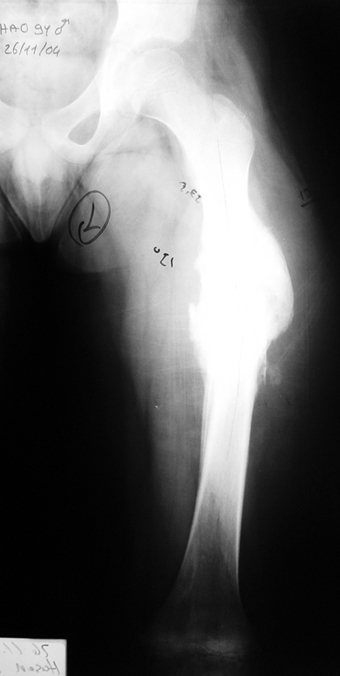

Chronic osteomyelitis leads to necrosis of bone and soft tissues. Dead bone is a nidus which hosts pathogenous microorganisms. Defence mechanisms of the host is usually not in optimum condition to deal with microorganisms. Antibiotics can’t reach the infection site because blood flow is disrupted. For these reasons, dead bone has to be completely removed by radical debridement.

Appropriate radical debridement necessitates excision of all necrotic bone and soft tissues, and frequently causes instability at the involved extremity. The remaining bone and soft tissue defect has to be fixed and reconstructed. The distraction osteogenesis method of Ilizarov is used successfully for achievement of union, correction of the deformity, elimination of limb length inequality and reconstruction of segmental bone defects.

Case 3